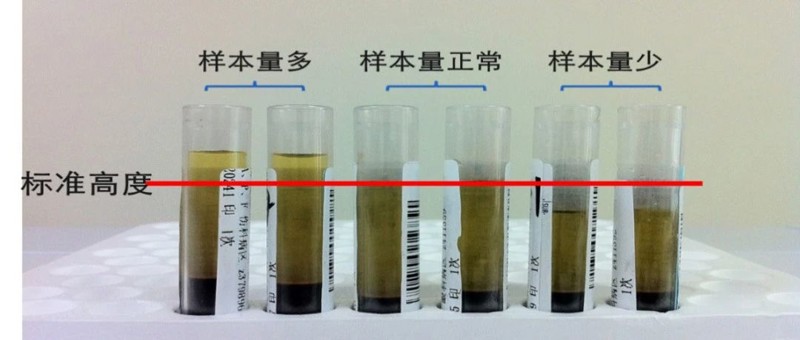

检验人需要知道的七大脂血处理方法,看完再不慌!